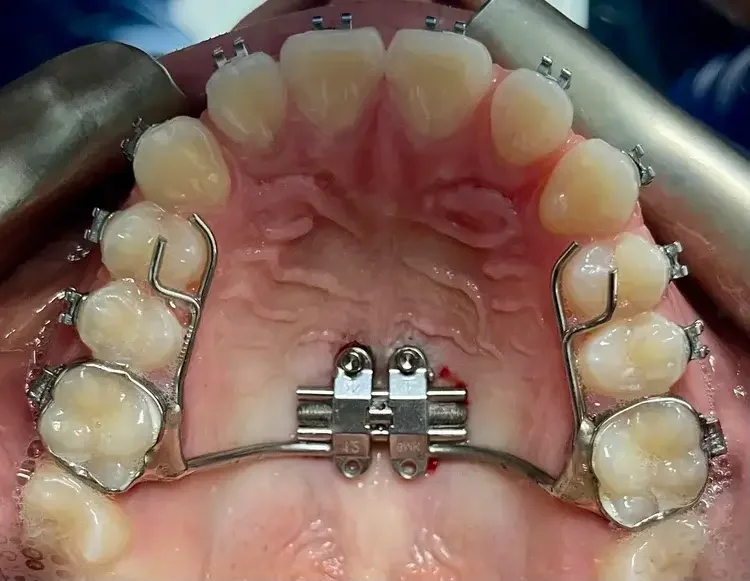

Mini-screw Assisted Rapid Palatal Expander (MARPE)

The MARPE appliance is a modern orthodontic device used to widen the upper jaw (maxilla) in patients where conventional methods may not be sufficient. Unlike traditional rapid palatal expanders (RPE), MARPE utilizes miniscrews that anchor to the palate, providing additional stability and direct skeletal expansion. This method is especially beneficial for older teens and adults whose jaw growth has slowed or stopped.

MARPE applies gentle, controlled pressure to separate the two halves of the upper jaw, expanding the mid-palatal suture. The miniscrews ensure the force targets the bones rather than just the teeth, promoting effective skeletal changes.

The appliance is custom-made and secured to your upper molars, with miniscrews inserted into the palate by your orthodontist or oral surgeon. Over time, gradual expansion creates more space, improving both function and appearance.